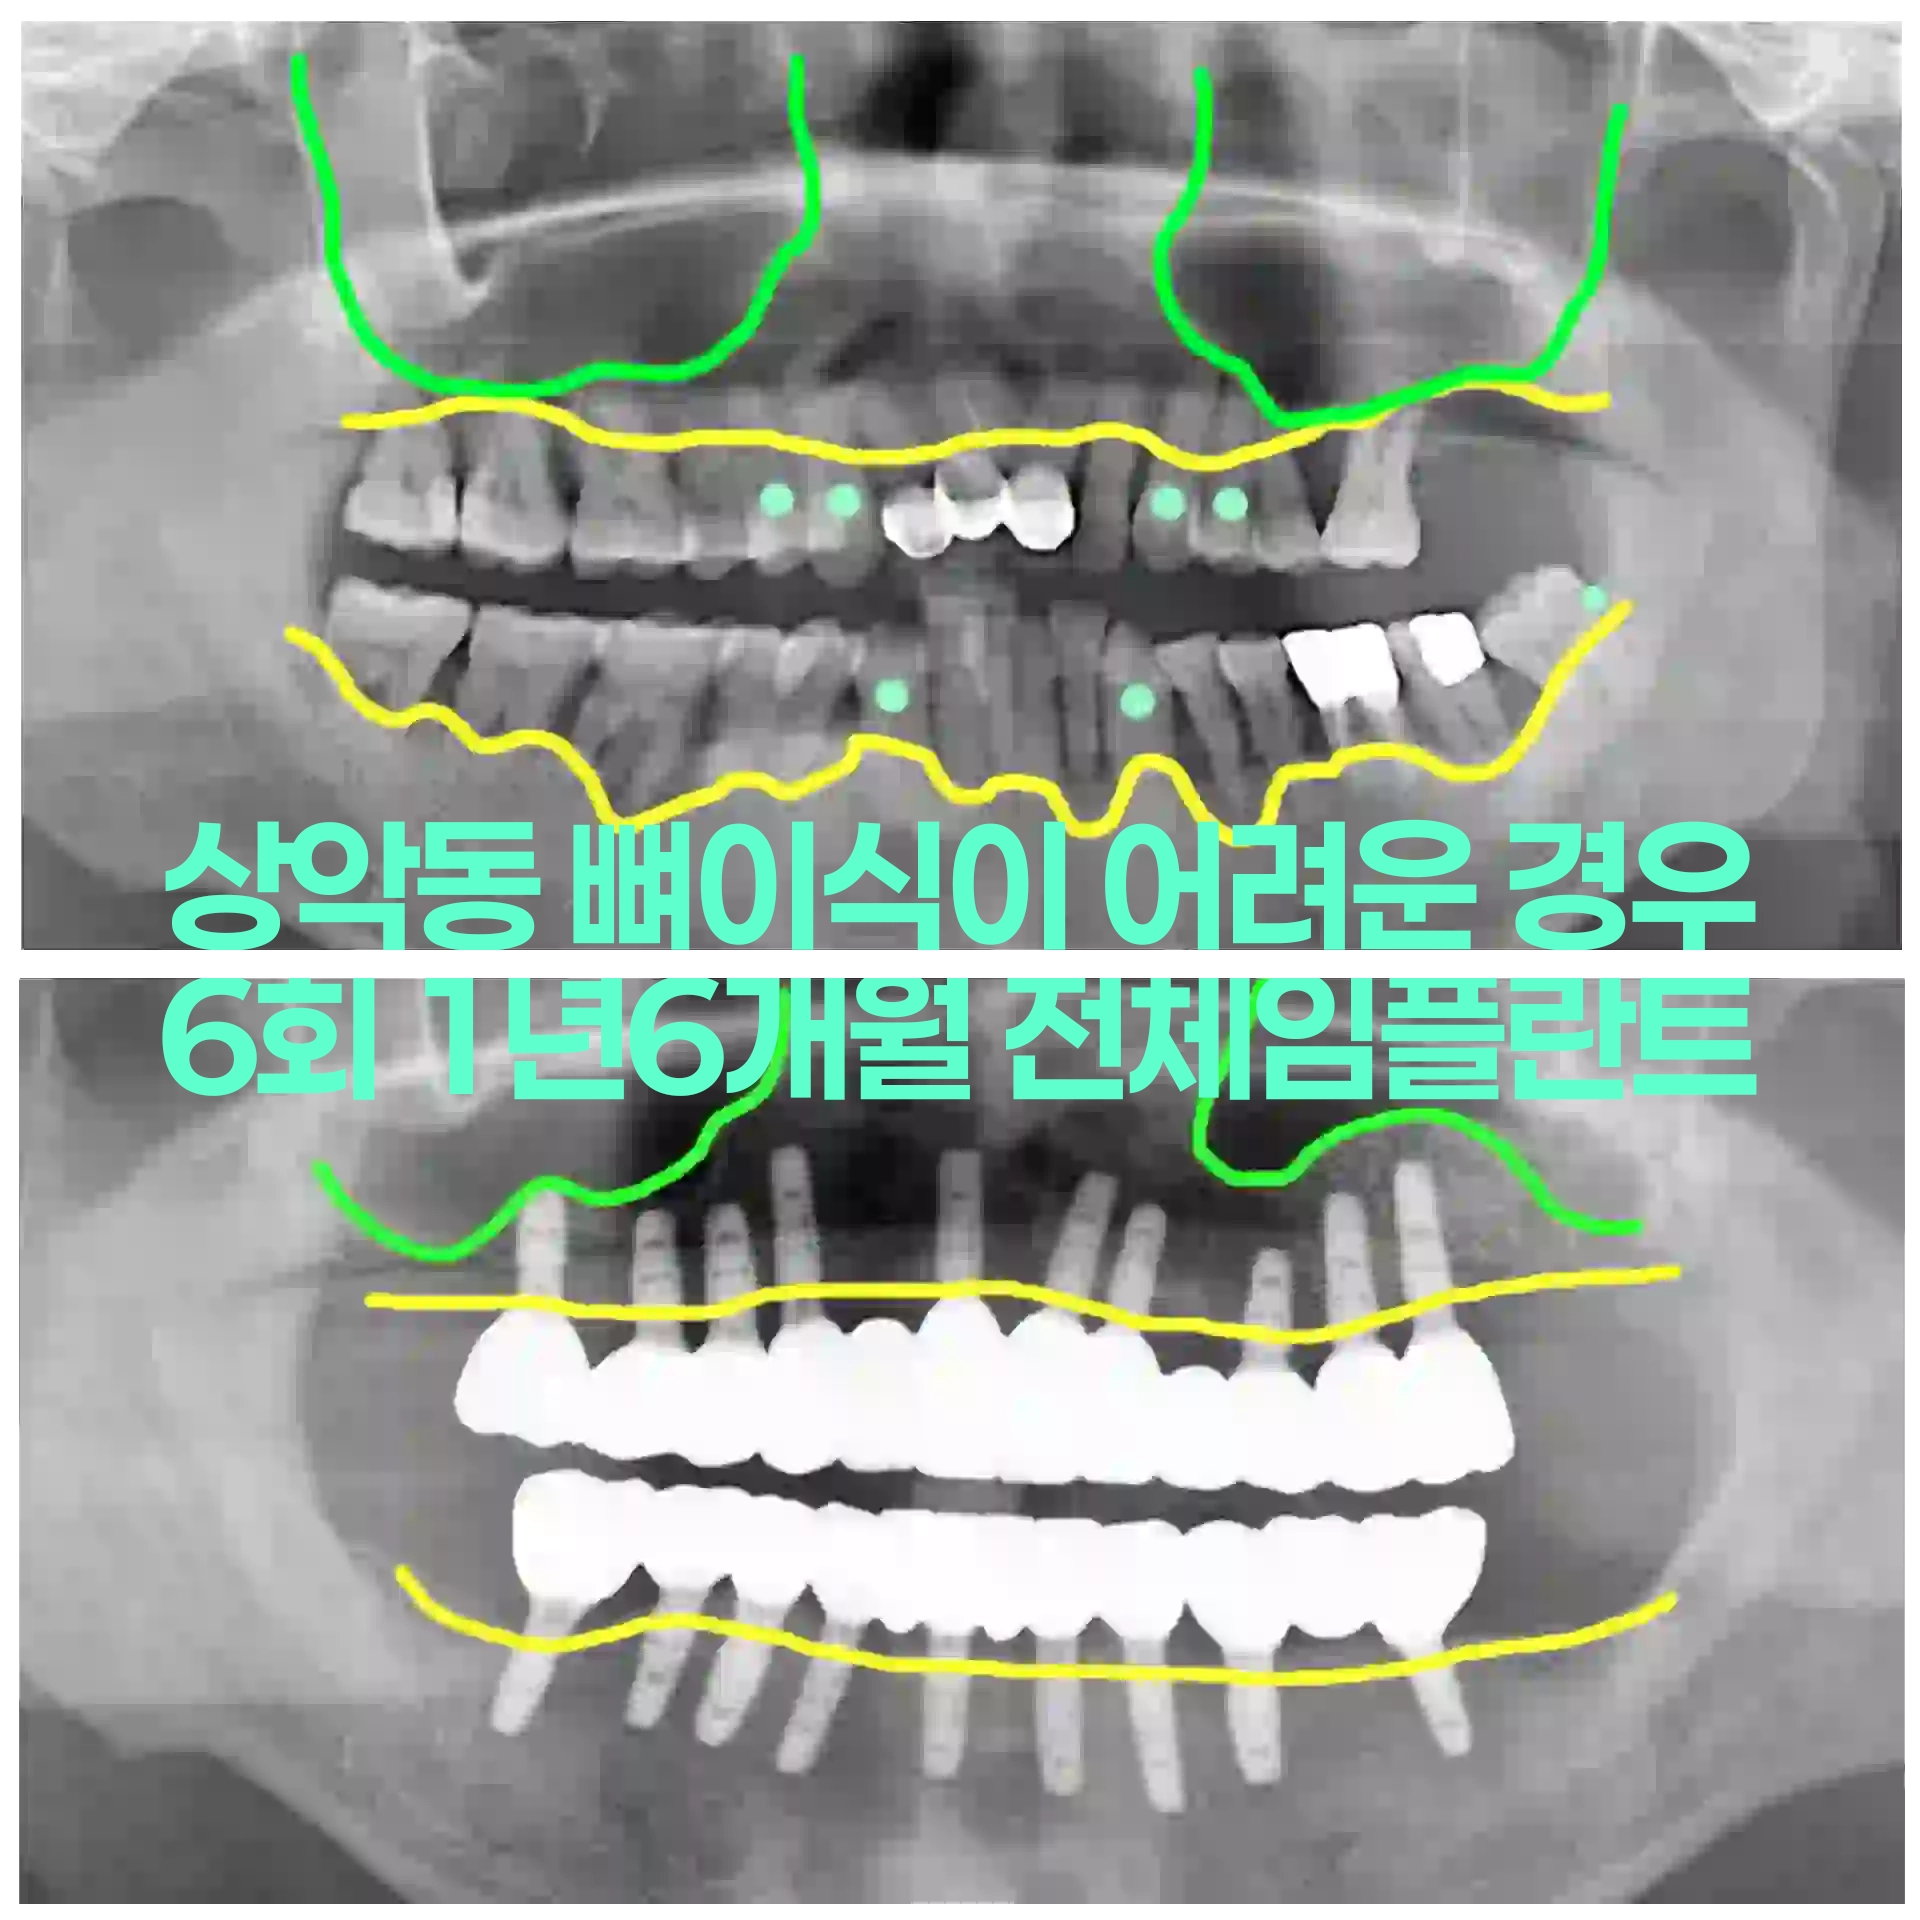

뼈가 많이 부족한 경우 상악동 뼈이식 동반한 전체임플란트 치료사례 6회 내원 치료기간 1년

확인하기 →

2025-11-15